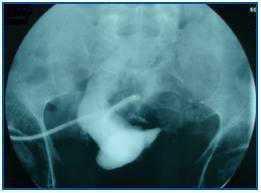

In December 2006, at the patient¿s request and due to significant vascular access difficulties, we decided to implant a peritoneal dialysis catheter (abdominal CAT was normal), liberate lax adhesions during the procedure and verify catheter function whilst in the operating room.

At 15 days after implantation, the peritoneal catheter was malfunctioning and provoking difficulties during both infusion and drainage. The peritoneography showed an image similar to that described for the previous case (figure 2).

The patient made the definitive transfer to HD once the catheter was removed; multiple adhesions were observed.

Figure 2.